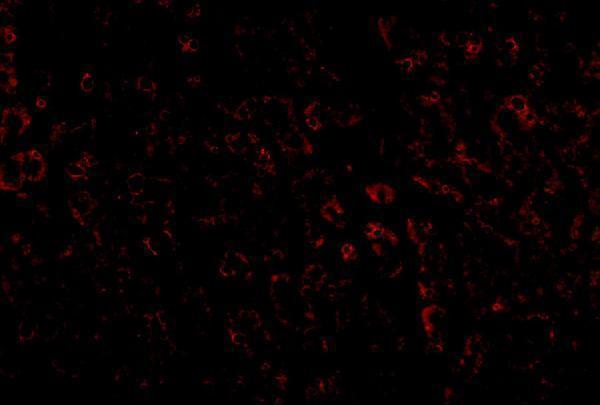

| Gene Name: | LDLR |

| Uniprot: | P01130 |

| Entrez: | 3949 |

| LDLR family |

Cell membrane; Single-pass type I membrane protein. Membrane, clathrin-coated pit. Golgi apparatus. Early endosome. Late endosome. Lysosome. Rapidly endocytosed upon ligand binding.